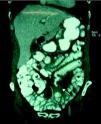

Linfoma T en paciente con enfermedad celíaca del adulto

T cell lymphoma in a patient with adult celiac disease